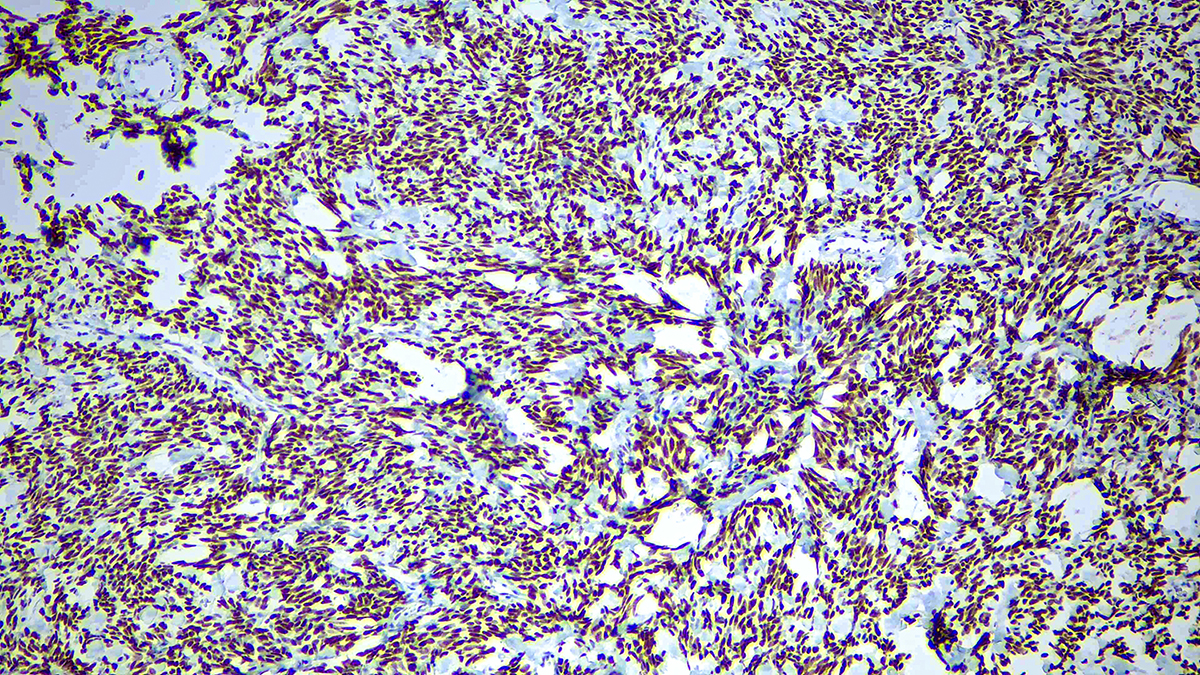

Solitary fibrous tumor (SFT) is a fibroblastic neoplasm of variable biologic potential that can arise at a wide range of anatomic sites. Almost all cases of (98%) including conventional, cellular, atypical, and malignant variants showed nuclear expression of STAT6. Staining for STAT6 was usually diffuse: 68% of cases showed reactivity for STAT6 in 75% of tumor cells. Further, the intensity of staining was strong in 67% of cases, moderate in 25%, and weak in only 7%. The heterogeneity of staining, both in terms of extent and intensity, which may be because of uneven tissue fixation or loss of antigenicity in older cases for which the unstained slides were stored for extended periods of time. All other tumor types examined were negative for STAT6, except for three dedifferentiated liposarcomas and one deep fibrous histiocytoma, which showed weak staining. STAT6 is therefore a highly sensitive and almost perfectly specific immunohistochemical marker for SFT, and can be helpful to distinguish this tumor type from histologic mimics.

| Positive Control Tissue | Solitary fibrous tumor |